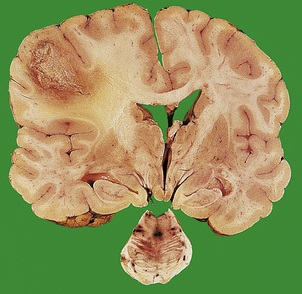

Herniations occur at several characteristic sites within the cranial cavity, depending on the site of the space-occupying lesion (Fig. 26.5). Transtentorial herniation is frequently fatal because of secondary haemorrhage into the brainstem (Fig. 26.6). This is a common mode of death in patients with large intrinsic neoplasms or intracranial haemorrhage.

image

Fig. 26.5 Sites of intracranial herniation. Space-occupying lesions in the cerebral hemispheres may cause herniation of the cingulate gyrus under the falx cerebri (1) or of the hippocampal uncus and parahippocampal gyrus over the tentorium cerebelli (2). Cerebellar tonsillar herniation through the foramen magnum (3) can occur with lesions in the cerebrum or cerebellum. A swollen brain will herniate through any defect in the dura and skull (4).

Fig. 26.6 Herniation effects in the brain. image A large haemorrhagic neoplasm (glioblastoma) is present in the right cerebral hemisphere, causing shift of the midline structures to the left and compression of the right lateral ventricle. image Transtentorial herniation at the base of the brain. A prominent groove surrounds the displaced parahippocampal gyrus (arrow). The adjacent 3rd nerve (N) is compressed and distorted and the ipsilateral cerebral peduncle (P) is distorted with small areas of haemorrhage.